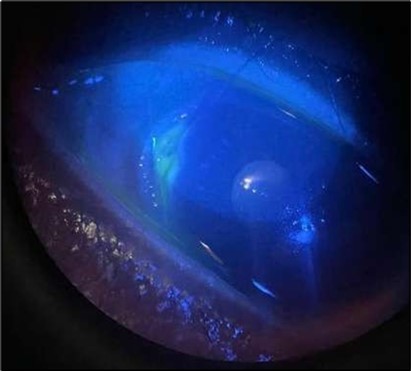

The patient was admitted and initiated on intravenous methylprednisolone 500 milligrams daily for three days, oral doxycycline 100 milligrams twice daily, oral vitamin C 500 milligrams twice daily, and a comprehensive topical regimen: moxifloxacin four times daily, fluorometholone four times daily, tacrolimus ointment three times daily, and preservative-free artificial tears. Gradual clinical improvement noticed over 72 hours, particularly in redness, inflammation and pain, but the epithelial defect persisted Figure 2.

Figure 2.OS, Slit-lamp image after a course of intravenous methylprednisolone therapy showing marked reduction in conjunctival hyperemia and stromal infiltration.

Despite systemic and topical management over one month, the epithelial defect persisted, indicating refractoriness to medical therapy. OCT imaging showed ulcer depth reduction to nearly 42% stromal thinning and width of 1180 µm, highlighting partial corneal healing. In view of the persistent ulcer and ongoing local inflammation, a conjunctival resection was performed to excise the perilimbal inflammatory focus and promote corneal repair Figure 3a and 3b.